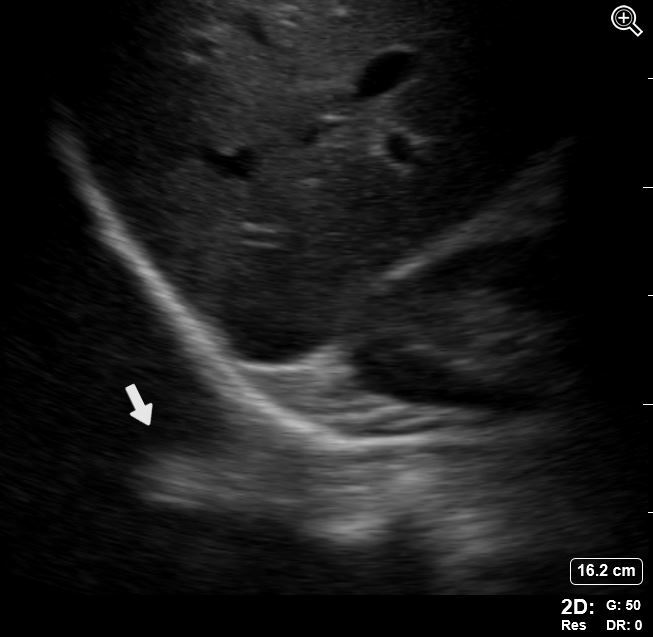

Instrumentation Refraction Artifacts Image